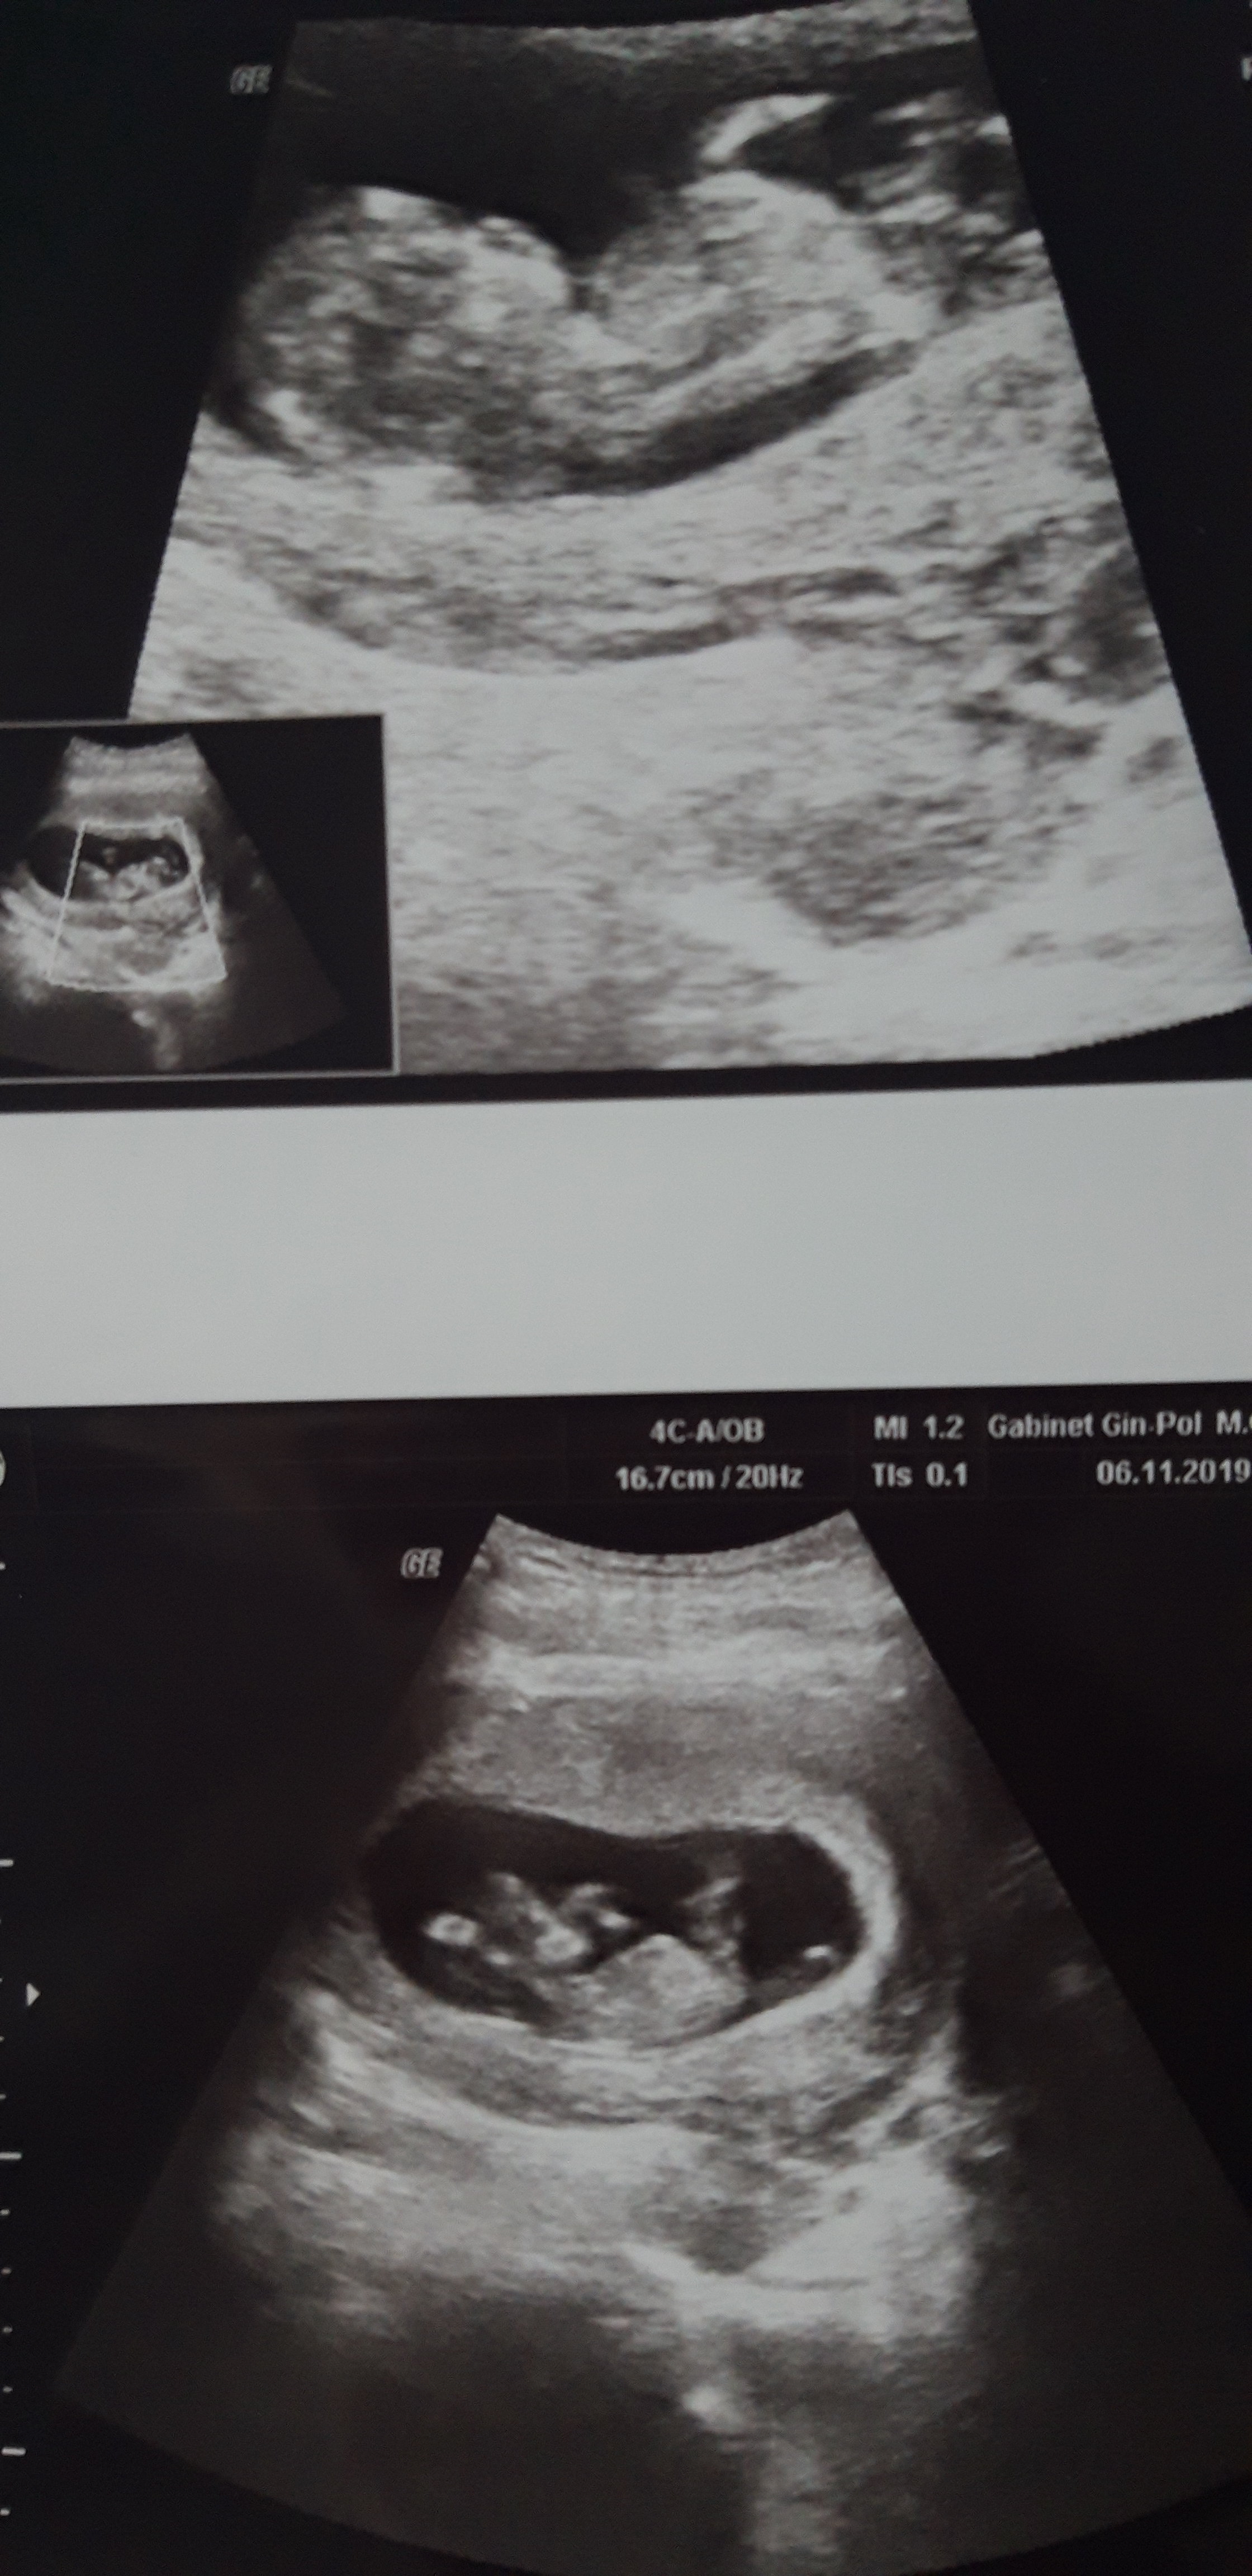

Nasze wizyty i zdjęcia USG :)

11+4

Na usg wiercił się niesamowicie, chyba zabiera mi całą energię bo ja chodzę półprzytomna ! No ale nie mam mu tego za złe ;) ;)